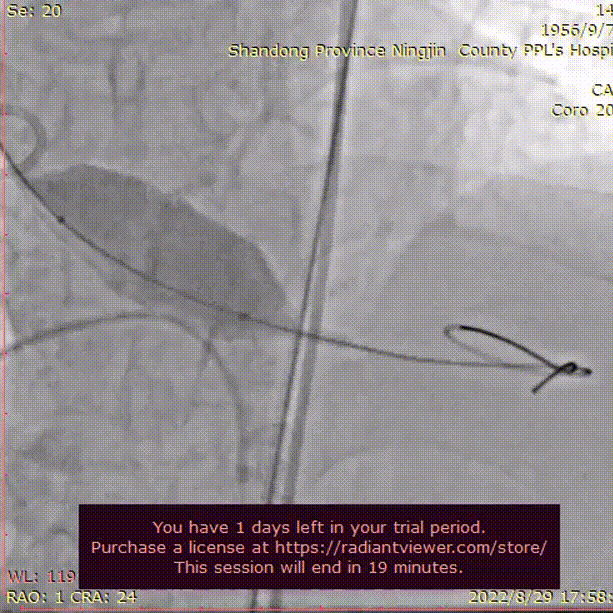

在Ecmo辅助下,行主动脉根部造影,猪尾确定选择最佳释放体位,观察瓣叶活动,确认是否合并反流,选择合适体位跨瓣。

主动脉根部根部造影

术者团队用25mm球囊预扩,结合瓣环及球囊预扩情况,预装AV29型号瓣膜。患者横位心,在抓捕器辅助下输送器过弓。

球囊预扩